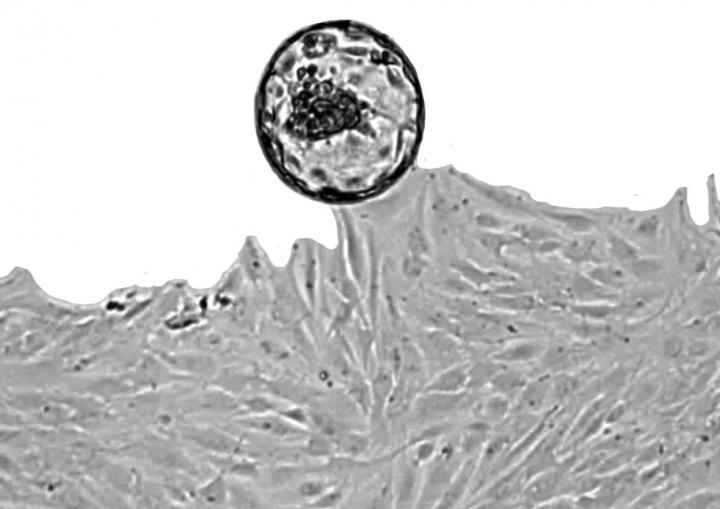

First the researchers discovered that the uterine natural killer cells remodel and refresh the lining of the womb at the time of embryo implantation. This is the first time a role for uterine natural killer cells in the lining of the womb has been identified outside of pregnancy.

In addition they discovered that this process isn't always balanced in each cycle. The natural killer cells perform the role of targeting and clearing inflammatory stressed cells, thereby making space for the implanting embryo. However sometimes not enough of these cells are cleared away and sometimes too many are targeted and removed. Excessive inflammation or insufficient clearance by uterine natural killer cells makes miscarriage more likely.

Their research is based on large amounts of experimental and observational data. They conducted an analysis of 2,111 endometrial biopsies, which is more than had ever been conducted previously. These were kindly donated by women who have attended the Implantation Research Clinic at UHCW NHS Trust. The research team examined the acutely stressed (acutely senescent) cells in the lining of the womb which generate tissue inflammation that is needed for embryo implantation. They found that the natural killer cells which are in the womb perform the important function of selectively targeting and eliminating acutely stressed cells. They perform this as the cycle progresses.